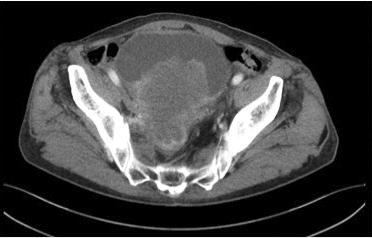

Figure 1

68Ga prostate specific membrane antigen (PSMA) PET/CT: presence of high suspicious area fo prostate cancer (SUVmax 20) in both lobe of the prostate (axial evaluation)

was performed from the skull base to the middle of the thigh Images were processed to obtain PET, CT, and PET CT fusion sections in the axial, coronal, and sagittal planes with a thickness of approximately 0 5 cm by two experienced nuclear medicine specialists, who were blinded to the clinical data The location of focal uptake on 68Ga PSMA PET/TC (Figure 1), three dimensional size, and standardised uptake value (SUVmax) values were reported on a per lesion basis with a sexstant scheme (apex, midgland, and base, each split into left and right) (5) All mpMRI (Prostate Imaging Reporting and Data System “PI RADS” version 2 ≥ 3) and 68GaPSMA PET/CT (SUVmax > 5 g/ml) index lesions underwent targeted cores (mpMRI TPBx and PSMA TPBx: four cores) com bined with extended systematic prostate biopsy (eSPBx: median 18 cores) (2, 14) The procedure was performed transperineally using a tru cut 18 gauge needle (Bard, Covington, GA, USA) under sedation and antibiotic pro phylaxis (17) Prostate targeted cores were obtained using a Hitachi 70 Arietta echograph (Chiba, Japan) supplied by a bi planar trans rectal probe (14) by one urologist with 10 years of experience in cognitive targeted biopsy Data were collected following START criteria (18)